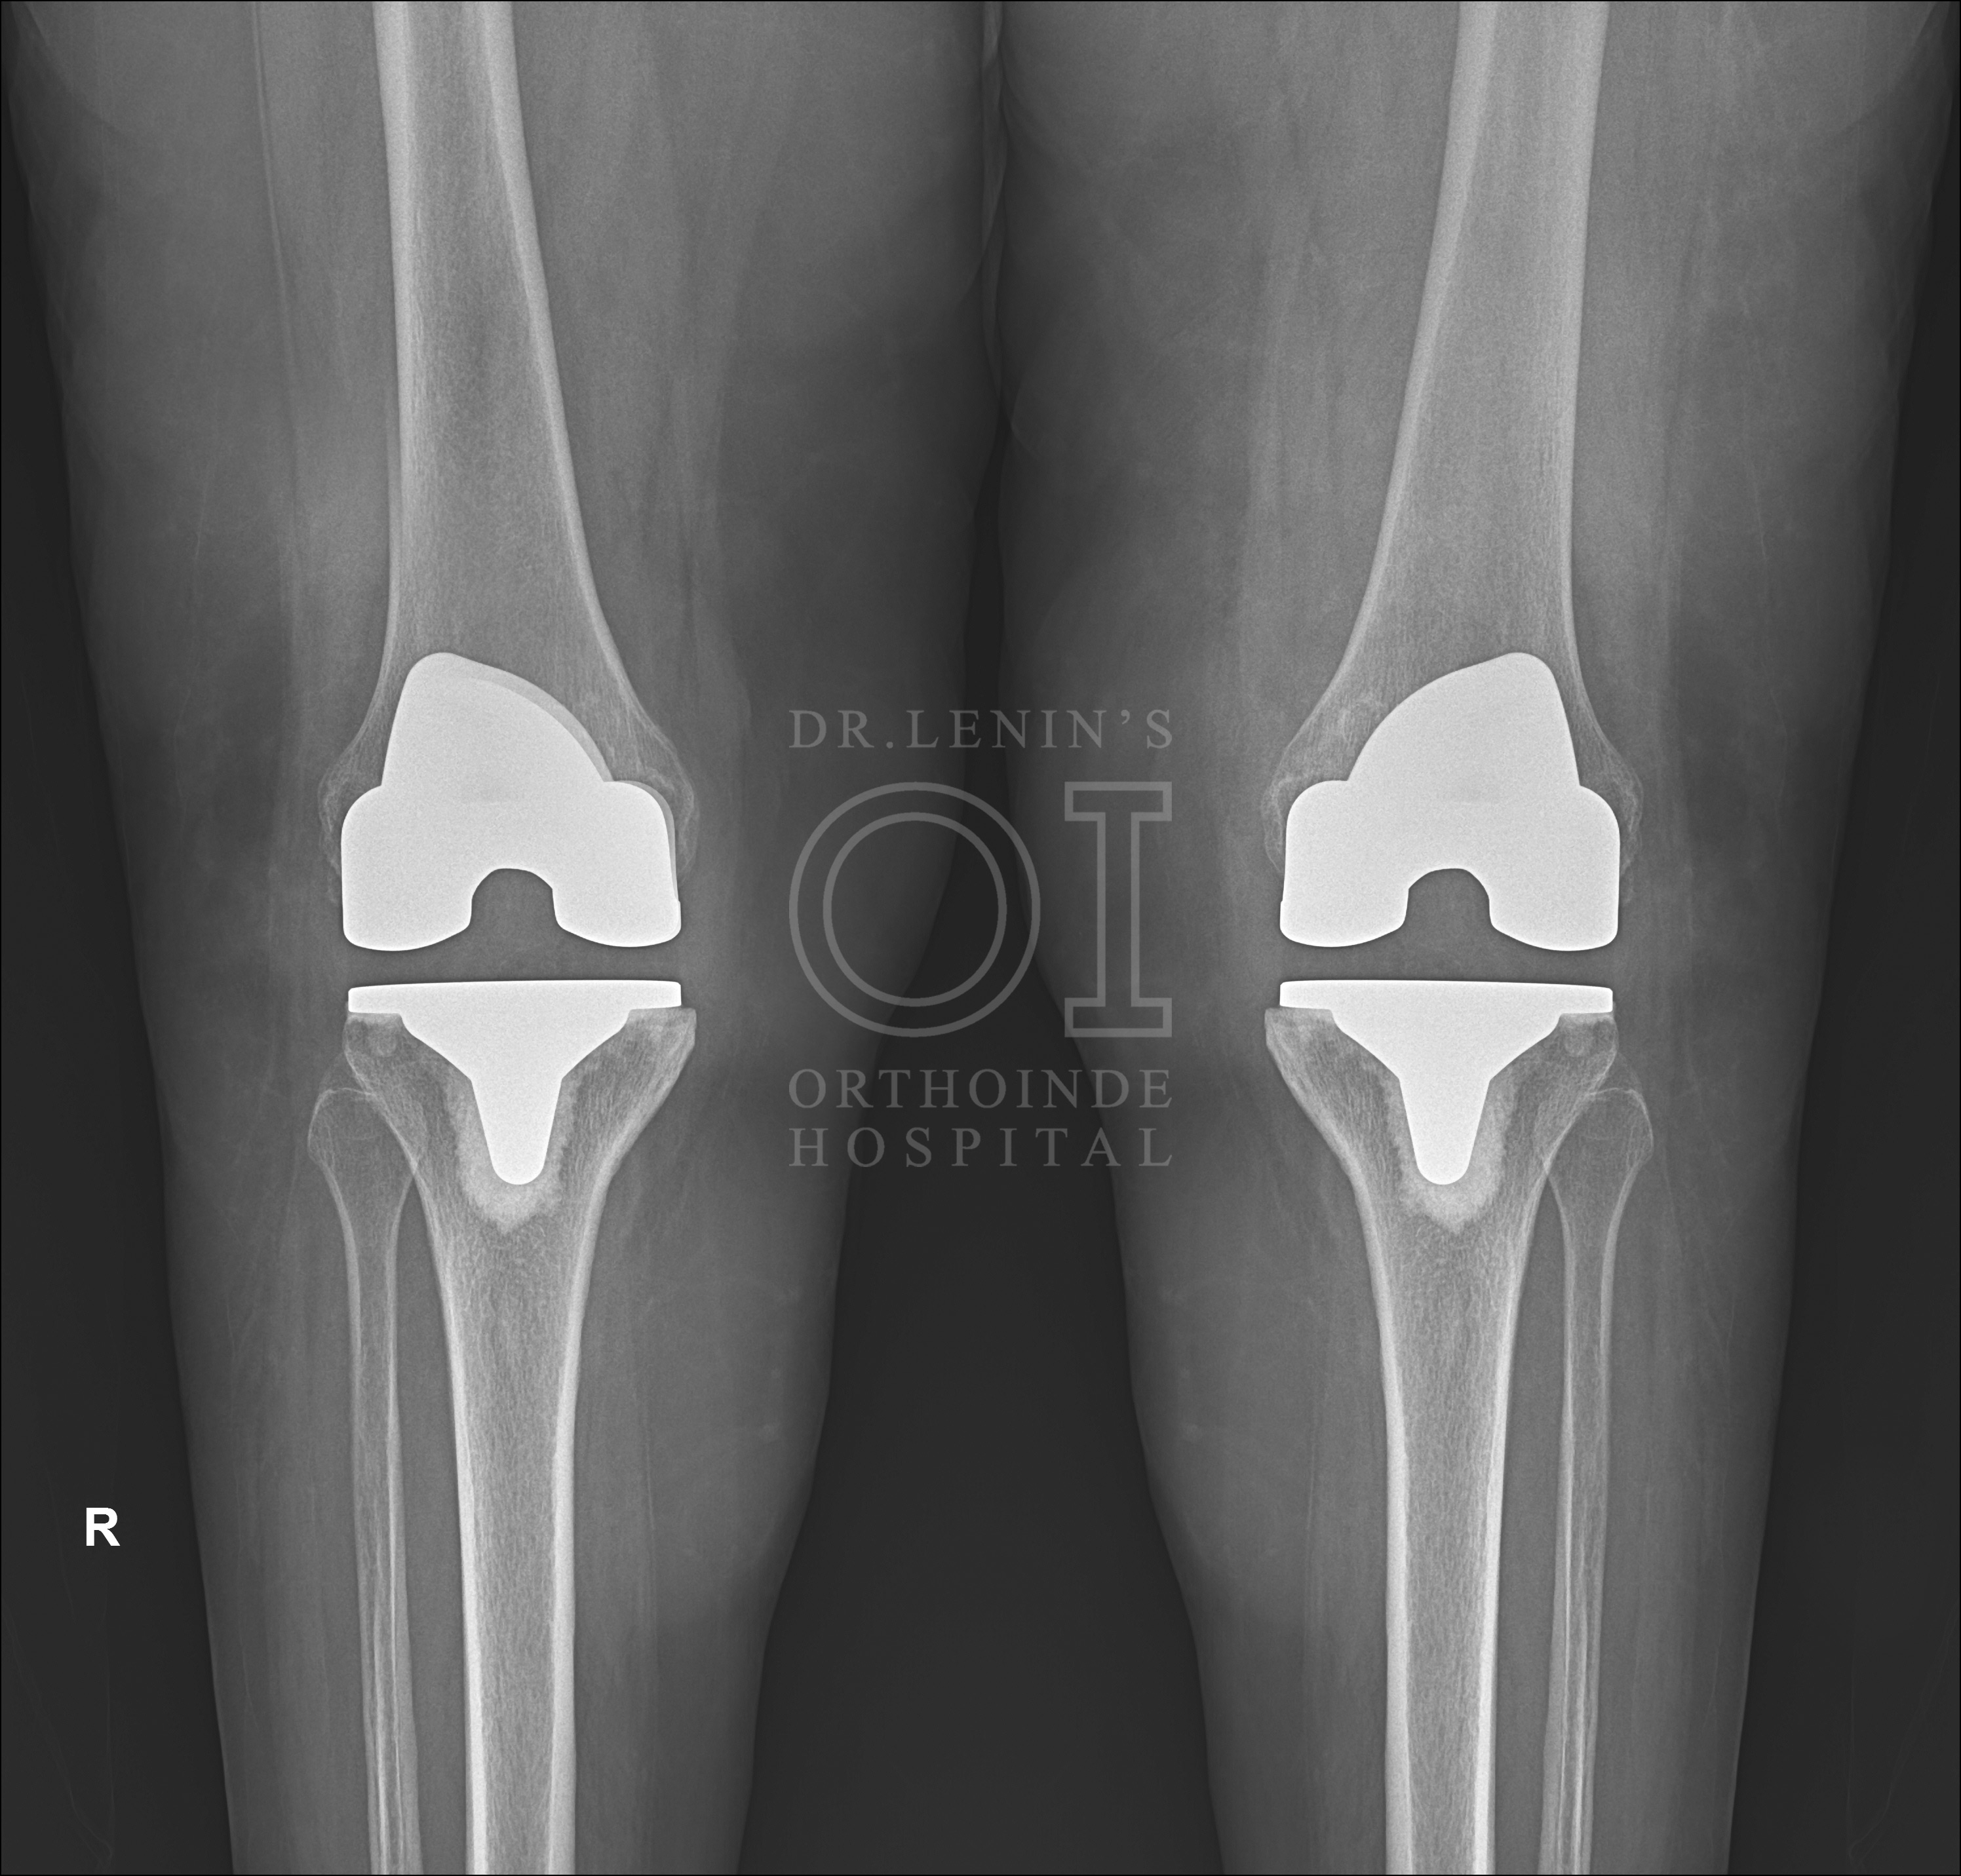

If the procedure is a simple replacement of the total knee, the surgery is called Primary Knee Replacement. Primary Knee Replacement surgery is also referred as Total Knee Arthroplasty or TKA in short

Minimally Invasive Primary Knee Replacement Surgical Procedure

In most of the primary knee replacement procedures, the joint surfaces at the end of thigh bone and the top of the shin bone are replaced. Sometimes the under surface of the kneecap (called the patella) is replaced with specialized plastic domes. But this decision is taken by the surgeon after studying individual cases. The orthopaedic surgeon always prefers to retain the natural patella. But if situation warrants then patella is replaced. At times, this decision is made during the surgery also.

Difference between Minimally Invasive Primary Knee Replacement and Conventional Primary Knee Replacement

- The incision made in conventional primary knee replacement is between 8 to 10 inches whereas in minimally invasive primary knee replacement, the length of the incision made is between 3 to 4 inches only.

- In conventional method the quadriceps muscle on the thigh is generally cut to expose the thigh bone. Whereas in minimally invasive method the muscle is lifted and pushed aside rather than making a cut. The quadriceps muscle is completely preserved in this method. The power in the Quadriceps muscles is the key in recovery after the surgery. Hence patients in minimally invasive method recover faster.

- In conventional method the shin bone is moved from its position (dislocated) vis-a-vis the thigh bone for fitting the prosthetics or implants. In minimally invasive procedure however, the shin bone is not dislocated from its position. This helps in faster recovery, and less pain after surgery.

- Similarly in conventional method, the patella or the knee cap is turned 180 degrees to get to the femur and tibia. In minimally invasive procedure however, the patella is just pushed aside. This helps in faster recovery, and less pain after surgery.